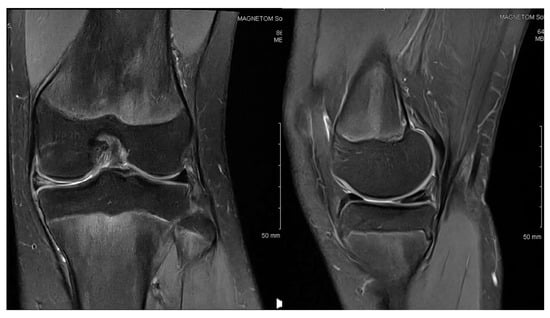

3.2. Case 2—S.C.S.